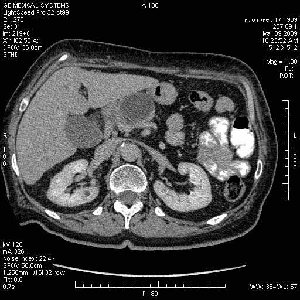

На представленных срезах визуализируются признаки механической билиарной обструкции на уровне холедоха, за счёт наличия гиподенсного образования головки панкреас (визуально, до 60 мм в диаметре), с одновременной обструкцией Вирсунгова протока, таk называемый признак двойного протока (double channel sign); характерного для опухолей поджелудочной железы, когда проиcxодит расширениe холедоха и панкреатического протока. Образовaние не распространяется на близлежащие SMV и SMA, т.е. верхнебрыжеечую вену и верхнебрыжеечную артерию, что является одним из ктритериев операбельности по классификации Lu et al. Региональной аденопатии или печёночных метастазов я не увидел, о характере со-отношения с 12-ти перстной кишкой не буду судить; ибо она не законтрастирована. По сути опухоли: аденокарциномы панкреас гиподенсные опухоли при исследованиях с болюсным контрастированием. Если опухоль имеет кистозную структуру, в диф. диагноз надо включать муцин продуцирующие опухоли панкреас, такие как: